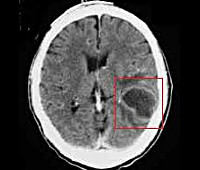

- Абсцесс головного мозга, мозжечка – патологические полости, ограниченные пиогенной мембраной и заполненные гнойными массами. Типичное расположение при отогенном происхождении – височная доля, мозжечок.

- КТ или МРТ головного мозга. Исследования дают возможность четко визуализировать локализацию абсцессов или очагового энцефалита, определить их размеры, выявить перифокальный отек, дислокацию и деформацию желудочков мозга. Контрастные методики показаны при подозрении на тромбоз кавернозного или сигмовидного синуса.